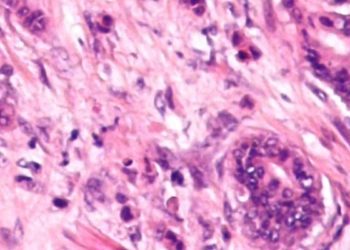

Strictures occur in an estimated 15-30% of Crohn’s Disease (CD) patients within the first 10 years after diagnosis. Several methods have been developed for evaluating small-bowel strictures, including computed tomography enterography (CTE) and double-balloon enteroscopy (DBE). CTE is very effective at detecting small-bowel disease, with a sensitivity and specificity of 83% and 88% respectively. Meanwhile, DBE has the benefit of allowing direct visualization while obtaining biopsies for histopathologic analysis. However, the relationship between symptom severity and the strictures detected through DBE is unknown. Therefore, this prospective cohort study aimed to determine the detection rate of DBE for CD patients with small-bowel symptomatic strictures. The study participants were enrolled from a single centre in China. All received both CTE and DBE, within one month of each other. The symptom severity was assessed through the Crohn’s Disease Obstructive Score (CDOS), with patients divided into low severity (scores 1-3) and high severity (scores 4-6). In total, there were 165 CD patients included, 42.4% of whom had low severity symptoms. The study found that detection rates of 92.7% and 85.5% through DBE and CTE respectively. For DBE, the rates were 91.4% and 94.7% in the low severity and high severity groups respectively (p = 0.13), whereas for CTE, the detection rate was greater in the high severity than the low severity group (90.1% and 75.9% respectively, p = 0.01). Overall, this study demonstrated that DBE is a very effective method for diagnosing small-bowel strictures in CD patients, with no difference depending on symptom severity.